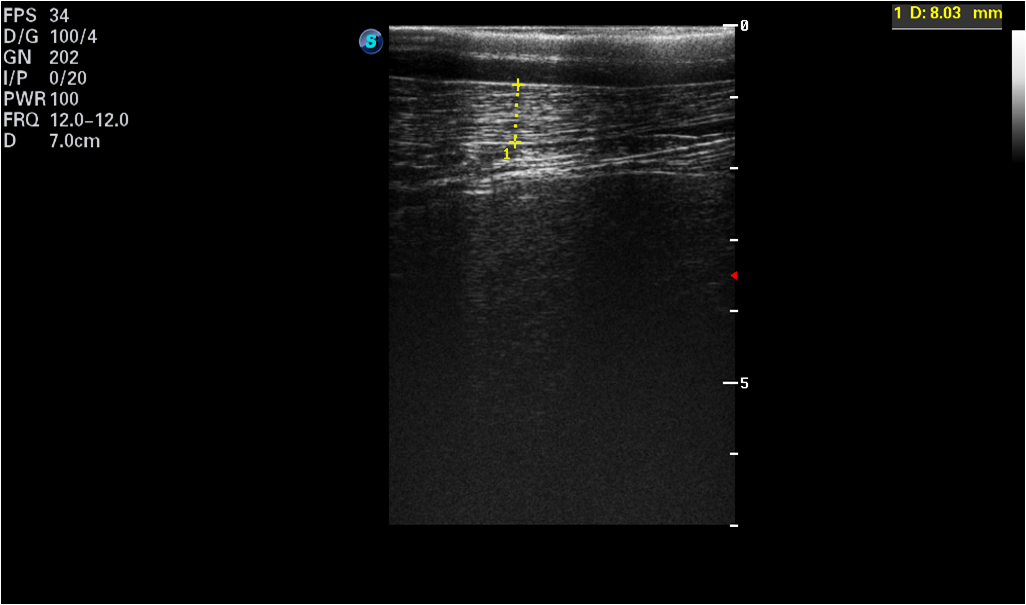

[ cap = Animal features, caption = Measured features (meanSD) of horses (H.1-H.16) and donkeys (D.1-D.16): the length of hair coat and the thickness of the subcutaneous fat plus skin (SF-Skin)., label = tab:animalsft, pos = h] lcc \tnote[]Different superscript letters indicate significant differences between Horses and Donkeys for Hair coat (a, b) and SF-Skin (c, d) respectively according to the Mann-Whitney-Wilcoxon (MWW) test\FLAnimals&Hair coat [cm]SF-Skin [mm]\MLDonkeys\tmark[a]\tmark[c]\NNHorses\tmark[b]\tmark[d]\MLp-value\LL After each IRT imaging, the ultrasonographic image was taken with an ultrasound scanner (SonoScape S9, SonoScape, Shenzhen, China) using a linear 5-12 MHz transducer (L752, onoScape, Shenzhen, China). Ultrasound scans were performed with the transducer placed at the animal´s back, over the 3rd lumbar vertebra, perpendicular to the backbone; all the images were collected on the left side of the animal [24]. The hair was trimmed at the measurement place and ultrasound gel (Aquasonic 100, Parker, USA) was used as a coupling medium. The real time ultrasonographic examination was freezed, the image was saved, and the subcutaneous fat (SF) plus skin thickness (SF-Skin) measurement were obtained. An example of an ultrasonographic image is presented in Fig.1. The hair coat samples were taken from the midneck about 5 cm below the base of the mane. The length of individual hairs were determined from a random sample of five pulled strands, including the roots [16]. Average hair coat length and SF-Skin values are presented in Tab. LABEL:tab:animalsft.